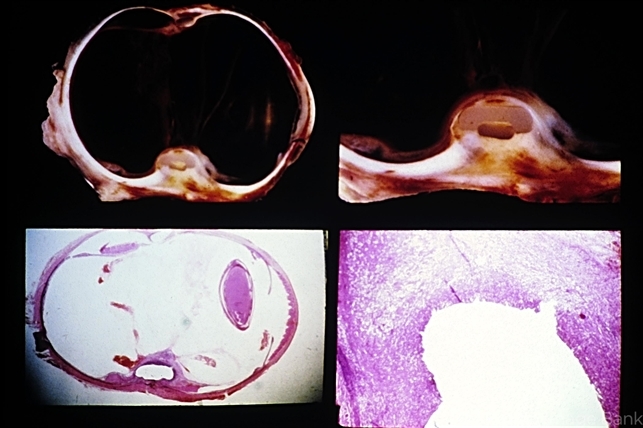

- Unit 09 Pathology of the Retina

- silicone plate, silastic band

- Internal erosion of silicone plate and silastic band. An intense acute and chronic inflammatory reaction surrounds the eroded silastic band (lower right). It was believed that the erosion of the encircling band and plate occurred as a result of its having been tied too tightly.